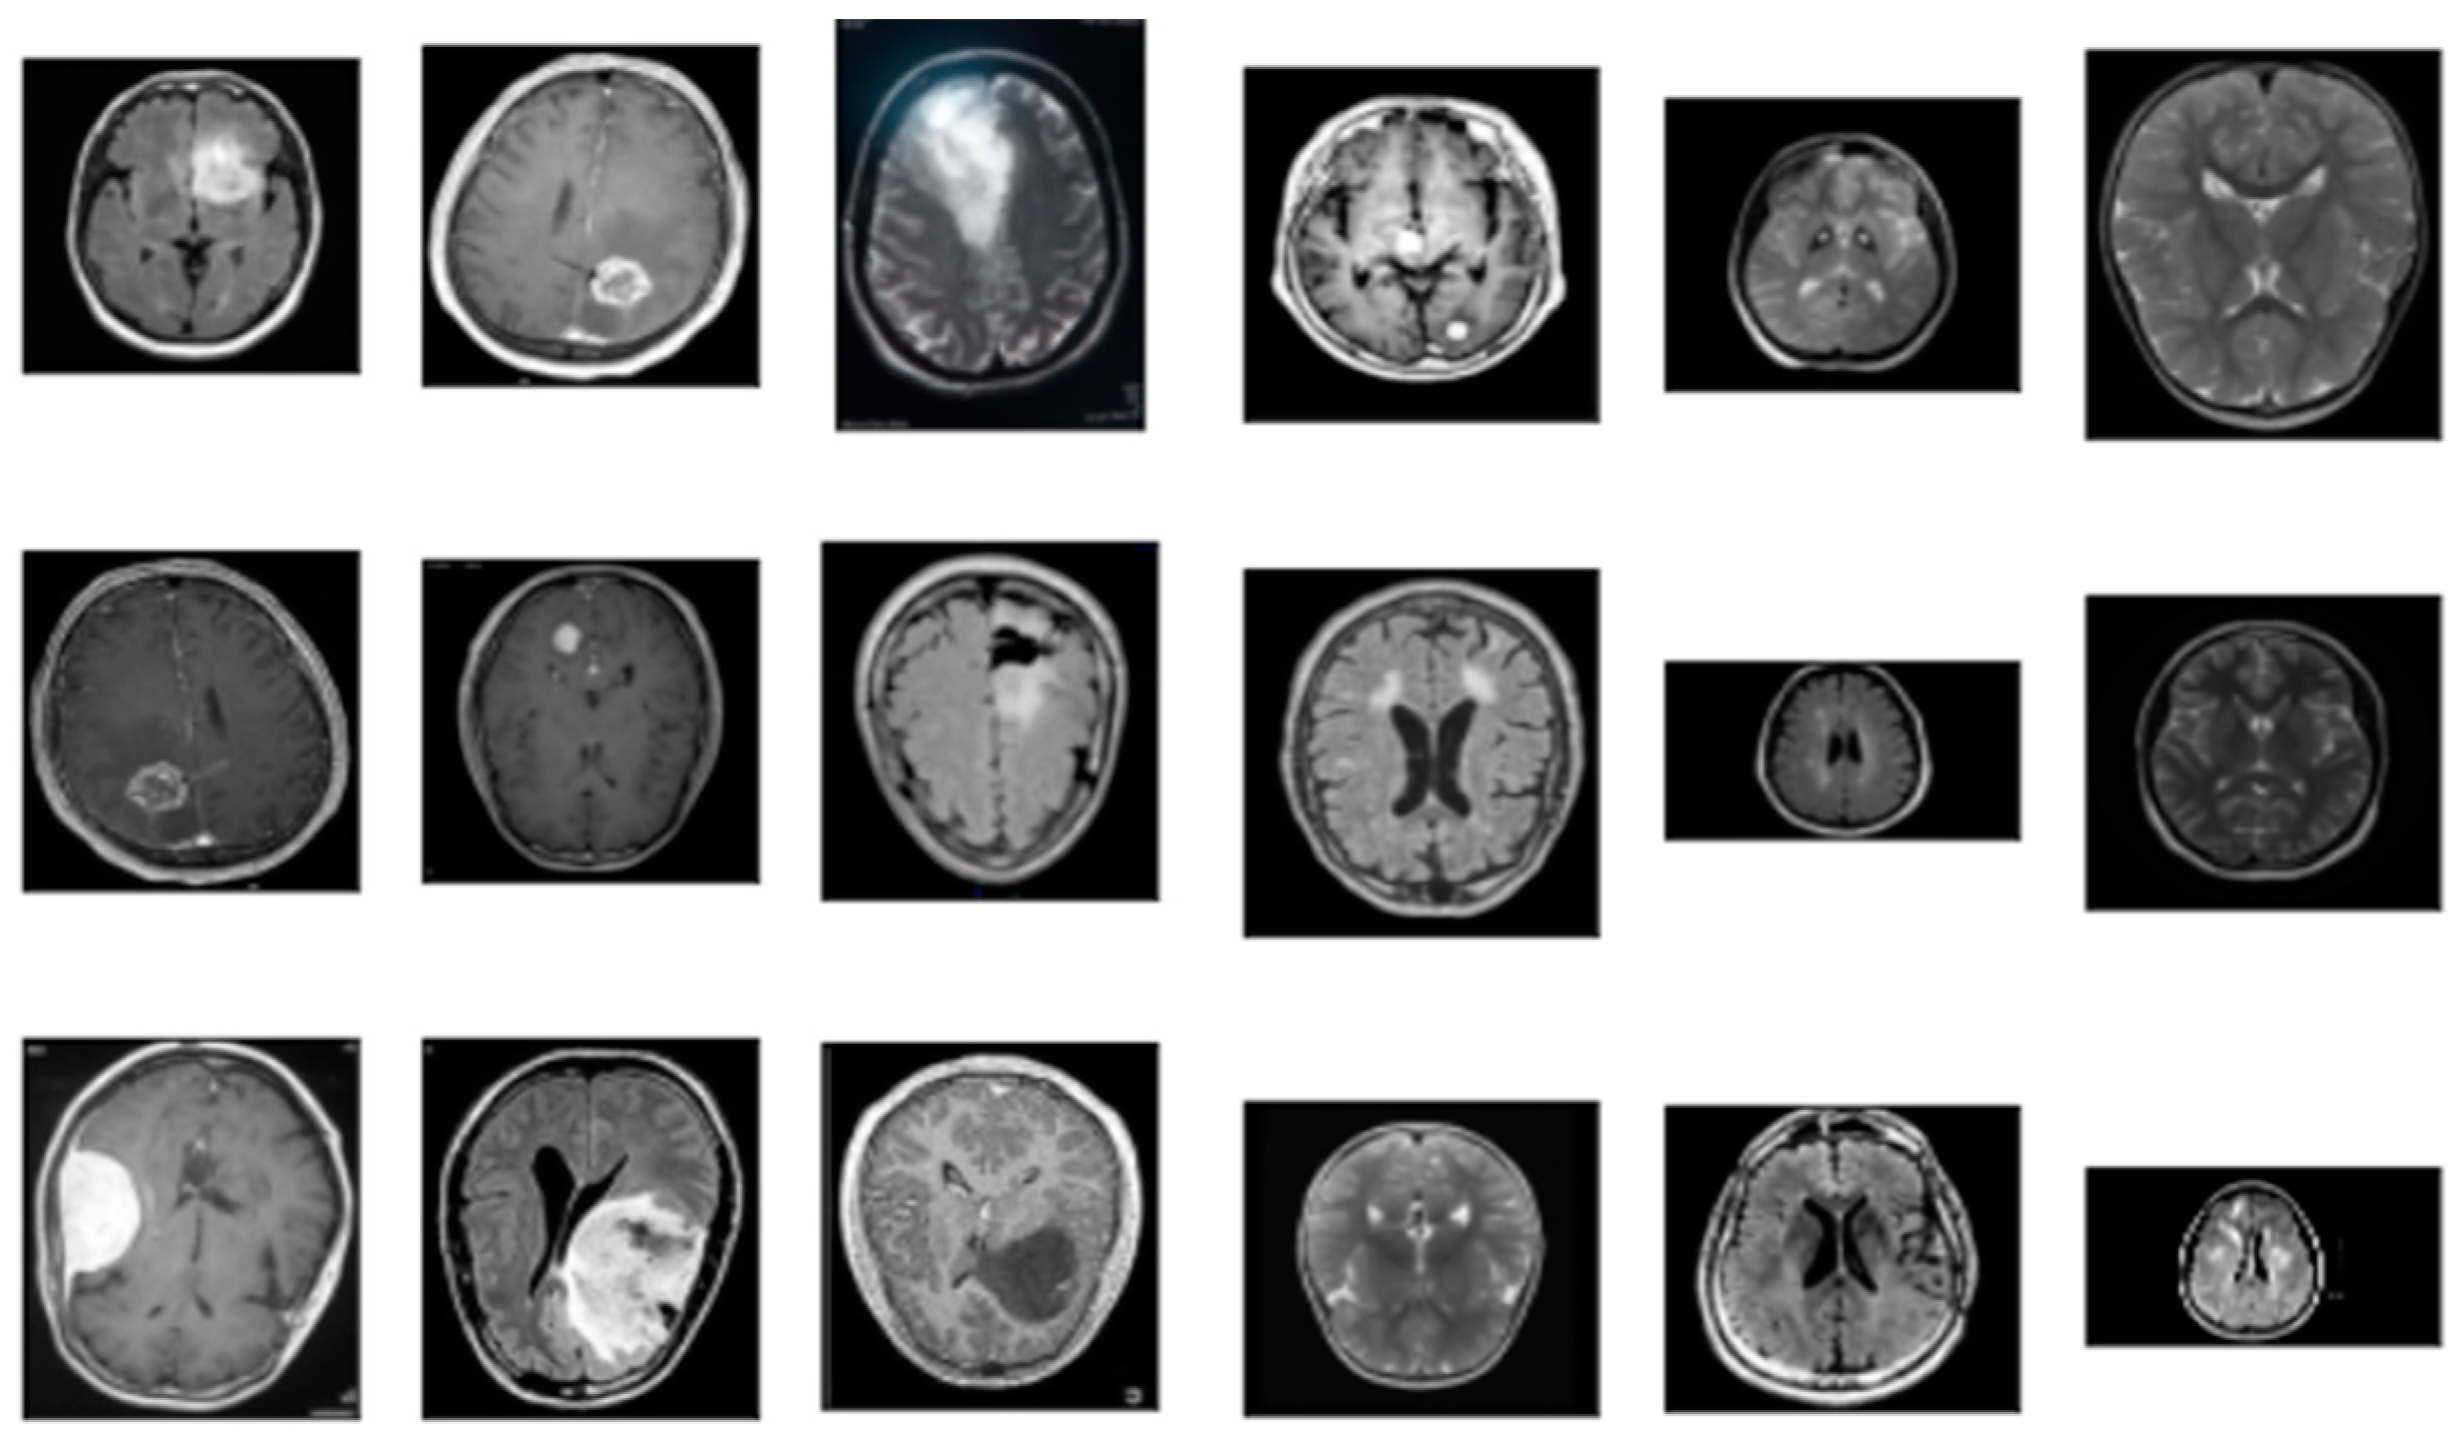

3.1. Data Collection

3.1.1. Data Preparation

| Folder | Description |

|---|---|

| Yes | Folder yes contains 1500 Brain MRI Images that are tumors |

| No | Folder no contains 1500 Brain MRI Images that are non-tumorous |

| Pred | This folder contains 60 Brain MRI Images that are both tumors and non-tumorous to be used to validate the model in the end |